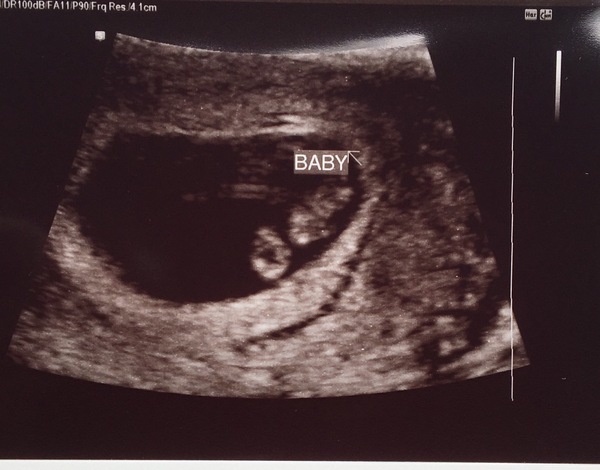

Wow @MrsDneedsaB great scan pic - baby looks huge! What's the CRL? Mine was 0.74cm at 6+4 and looked about half that size - it's amazing how quickly they grow!

No worries starshine your little bean is measuring larger than mine. It's currently 1.65cm at 8+1 not quite sure of the growth rate at this stage....could it grow 2mm in a day?

@MrsDneedsaB wow! What a scan pic! It actually looks like a little baby and you're only a week further along than me! I'm imagining my little blueberry becoming a baby over the next 7 days!

Here's my scan pic at 8w; I'm 9+2 now and feel so, so rough. Sick and really lightheaded, with a nasty taste in my mouth and a belly that is ravenous but nonetheless repulsed by all food. I can't wait to get past this bit! Roll on week 13...

@RosesForBadgers lovely scan pic!